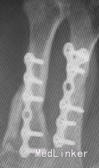

入院诊断左手损伤,左第2~5掌骨开放性粉碎性骨折,左第2~5指伸肌撕脱损伤,左手背软组织挫裂伤伴缺损,左中、小指指深屈肌腱断裂,左环指指深屈肌腱撕脱损伤,左手骨间肌、蚓状肌断裂、挫裂伤,左手指掌侧总神经、指背侧总神经及指神经断裂,左手指掌指总动静脉、掌浅弓、掌深弓断裂,左手掌软组织挫裂伤,左大小鱼际肌部分断裂,左桡骨下段横形骨折,左肘部软组织损伤。入院后给予急诊清创固定1周后左小指、环指缺血坏死,再次手术行左环、小指切除,左第5掌骨切除、左第4掌骨残端修整、左桡骨下端切开复位固定术,左第2、3掌骨骨折端术后5个月无愈合迹象。术后X线片提示:骨折断端存在间隙,骨痂很少或无,断端分离,髓腔封闭,骨质疏松,无骨小梁形成,符合骨折不愈合诊断。

该患者骨折不愈合处获得完全骨性愈合,临床愈合时间2个月。治疗过程中未出现针孔及深部感染。